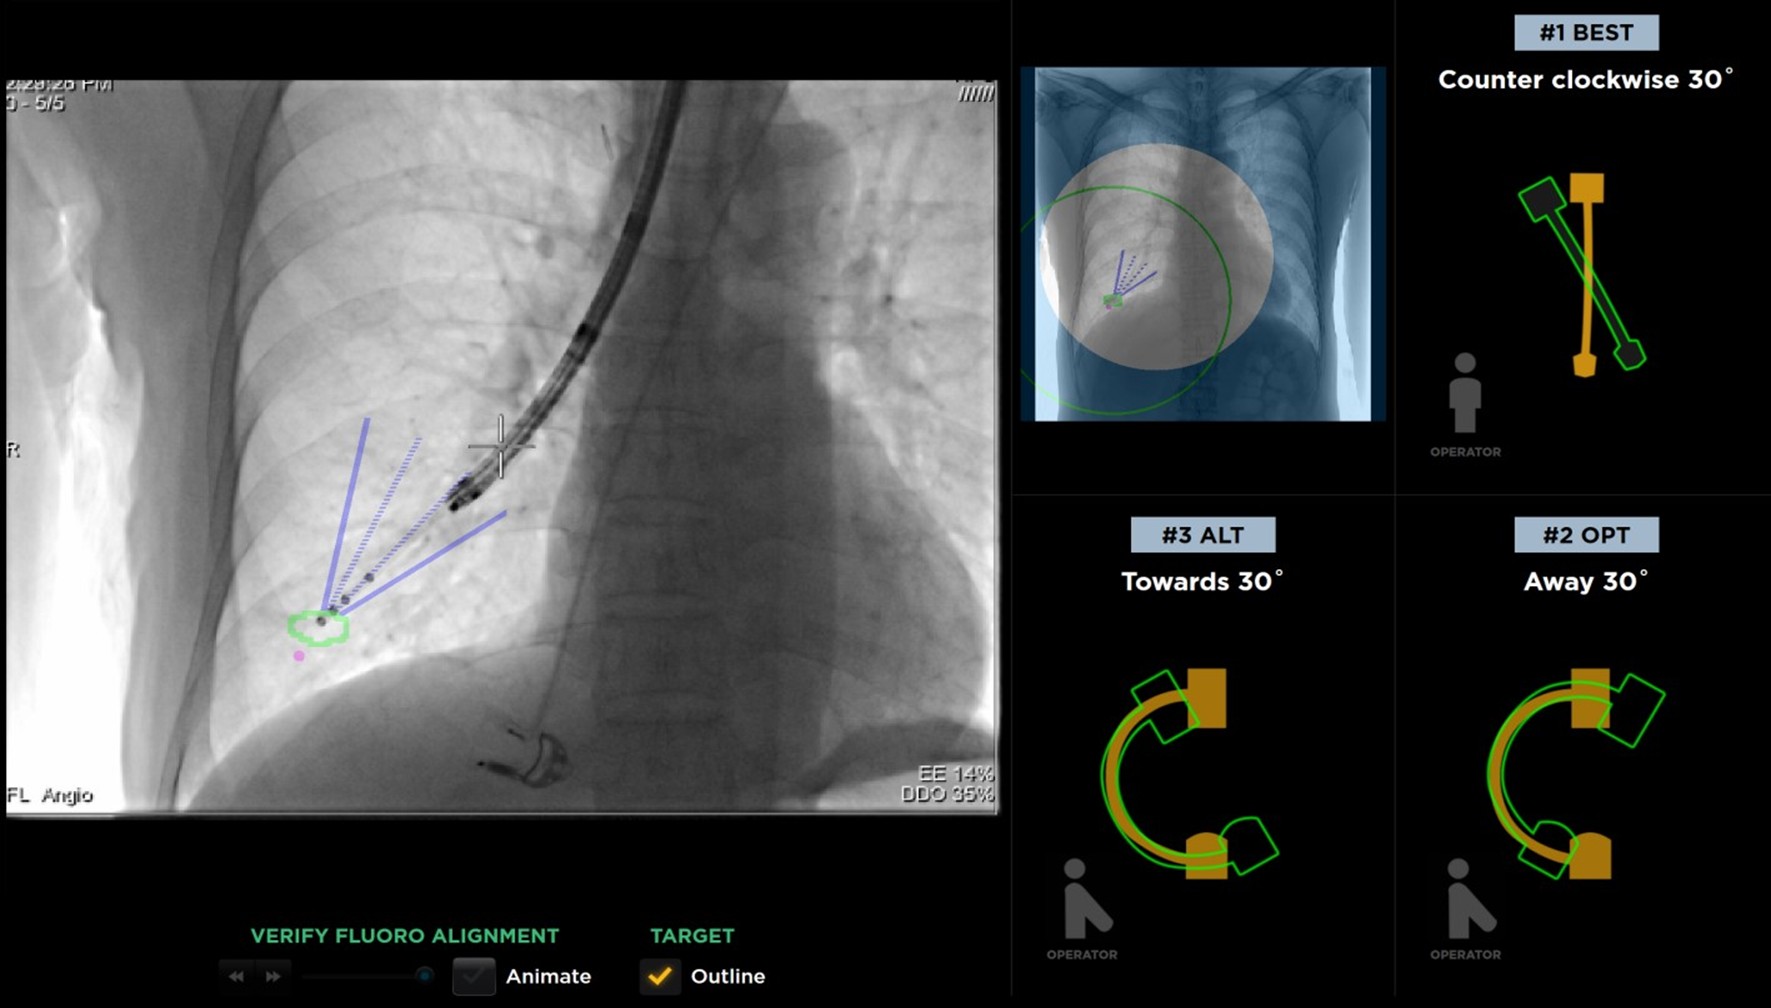

▲導航過程於複合式手術室(Hybrid Operating Room, Hybrid OR)藉由螢光透視平台 (Fluoroscopy)取得氣管外病灶組織, 提高安全性及診斷率